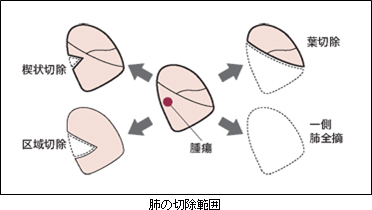

手術は腫瘍の占拠部位とその大きさで肺をとる範囲が異なりますが、術前に肺機能検査で術後の肺機能を予測した後、手術に耐えられるかどうかを判定して切除範囲(術式)を決定します。

患者さんが切除に耐えられれば(手術後も十分な肺機能があるなら)、“必要にして十分な”切除は腫瘍のある肺葉の切除と周囲のリンパ節を摘出(リンパ節郭清)する術式で肺がんの標準的な手術とされています。

肺部分(楔状)切除術はスリガラス陰影を伴う高分化型の早期肺腺癌の場合や高齢の方で重度の肺気腫などで肺機能が十分でない場合に対しておこないます。また最近、画像診断の進歩とともに増えてきている1cm前後の小型の肺がんに対しては根治性を損なわない範囲で肺区域切除とリンパ節郭清の術式を選択することがあります。

腫瘍の進展状況によってはやむを得ず肺全摘術を選択せざるを得ないこともあります。